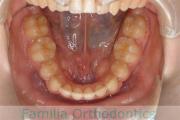

No.23V-061

- 主な症状:

- 叢生

- その他の症状:

- 上下顎前突

- 年齢:

- 23歳

- 性別:

- 女性

- 抜歯部位

- 上:

- 44

- 下:

- 主な使用装置:

- FEA 022

- 治療にかかった費用:

- 88万円

でこぼこを綺麗に並べたいということで来院されました。上下左右から小臼歯を抜歯して、マルチブラケット法を2年半、30回程度通院していただいて行いました。

かなり強い叢生(でこぼこ、凹凸、ガタガタ)のため、保定をしっかりしないと後戻りのリスクが高いケースといえます。

- ≫治療後

-